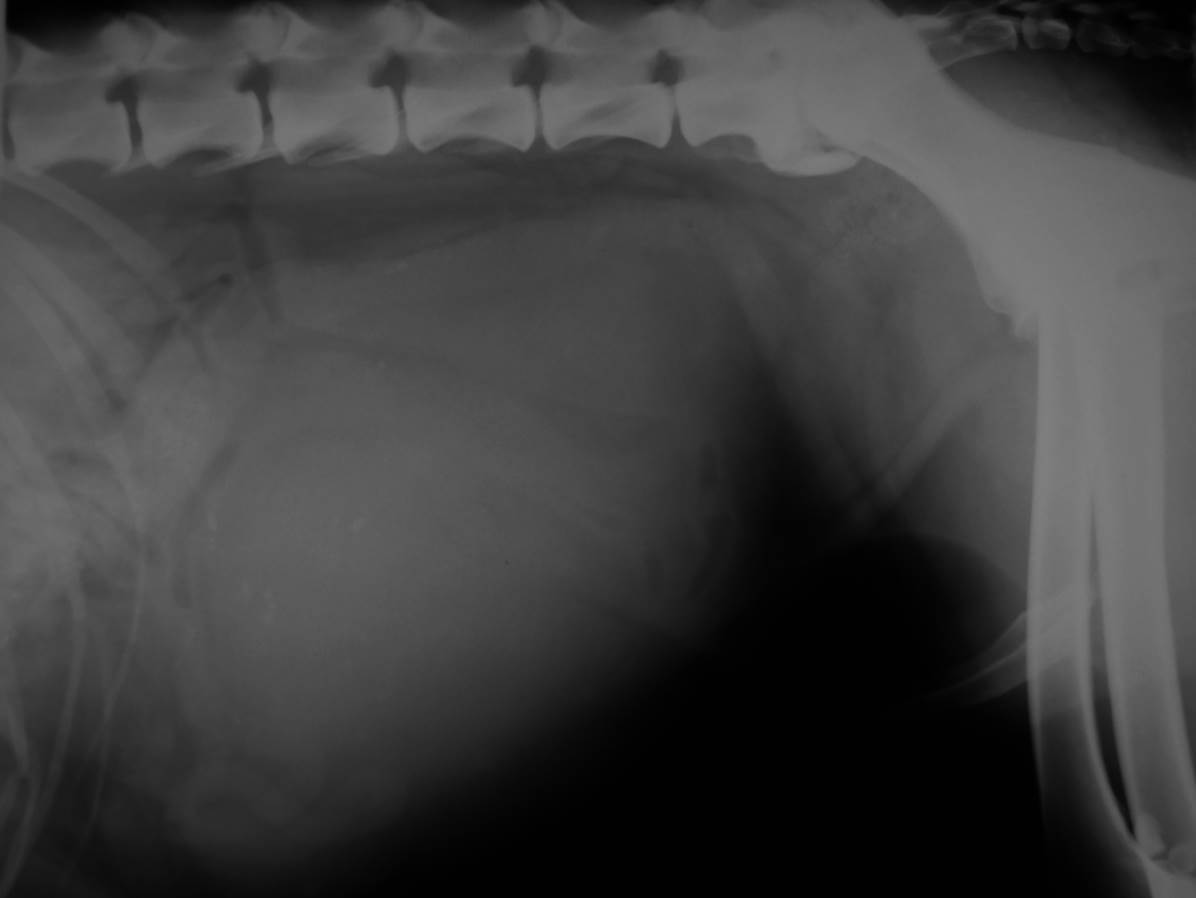

Case Beaver

Discuss this case?

•DCC and retrograde urethrogram

–poor quality urethrogram, poor filling of urethra, air bubbles ++. This study is important to rule out strictures, urethral plug, calculi.

•Bladder has identical appearance on both films

–small (likely not possible to distend further or at least not safely)

–thickened wall

–repeat retrograde to rule out stricture/urolith but doesn’t seem obstructed

–urinalysis especially for urine culture in case UTI following recent catheterisation during last episode of clinical signs

•Diagnosis: likely to be FLUTD, idiopathic cystitis